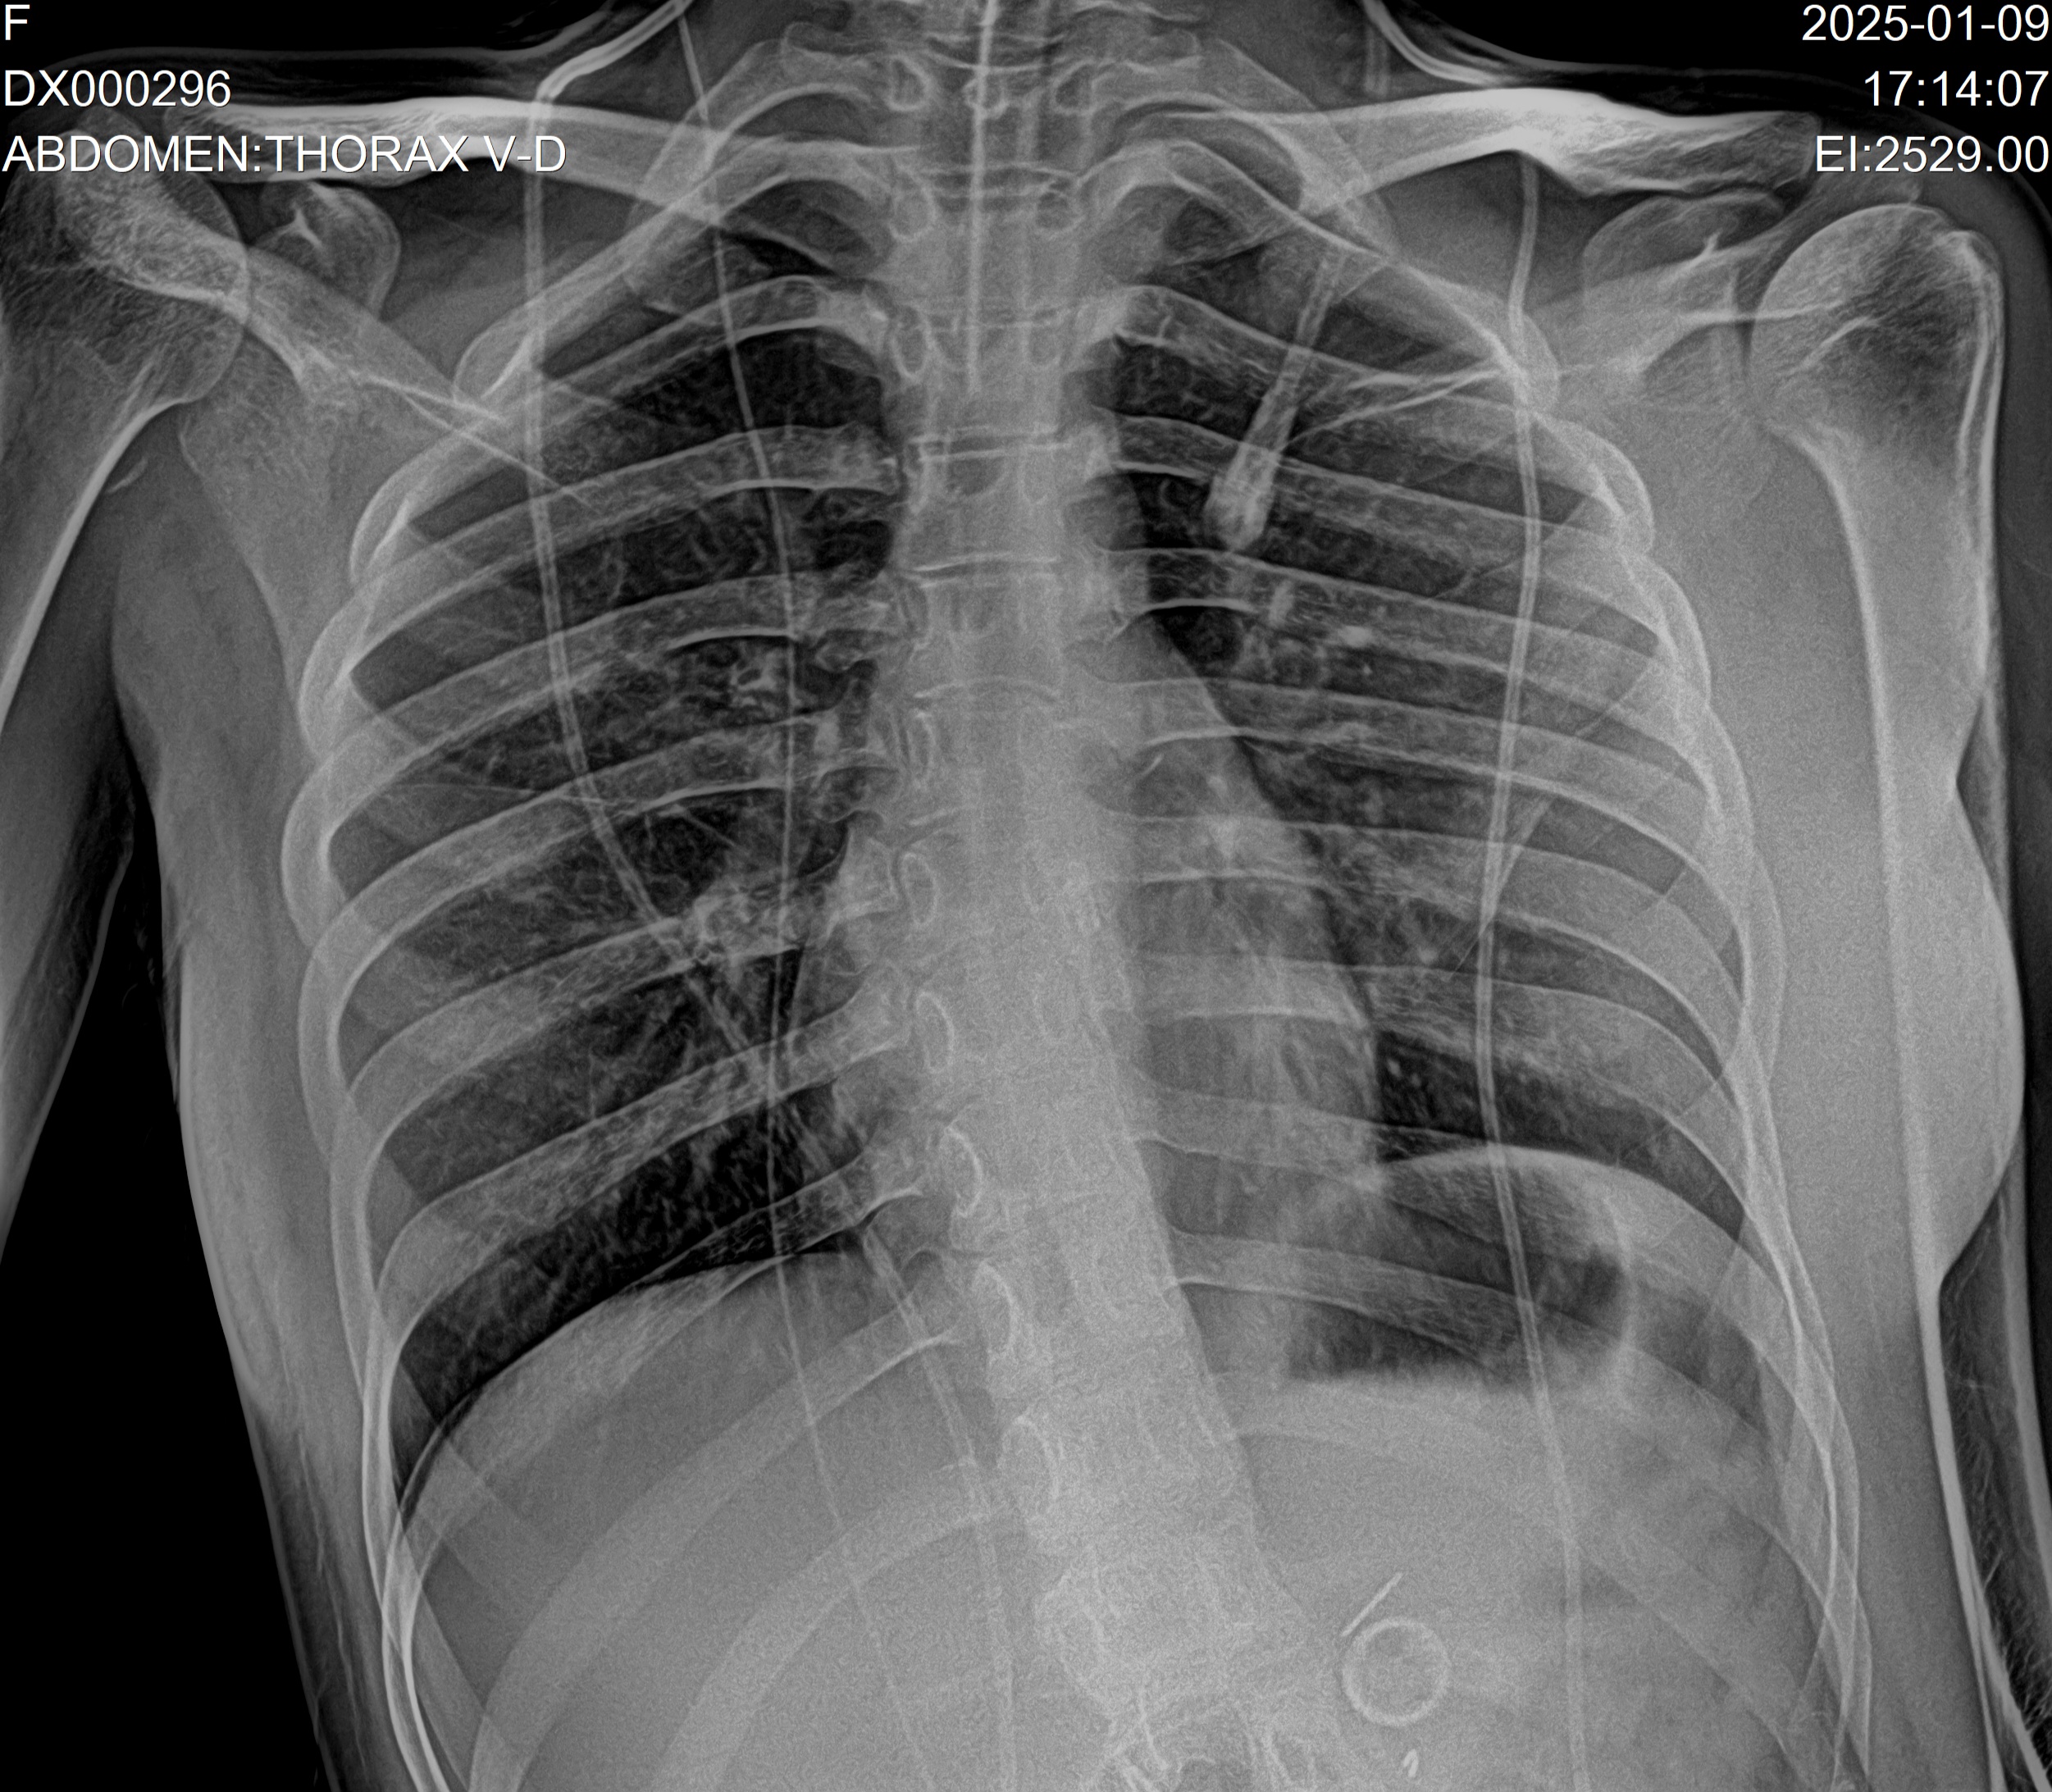

- Radiografías digitales humanas

- Controles postoperatorios y seguimiento de tratamientos

- Equipos digitales portátiles con calidad de centro médico